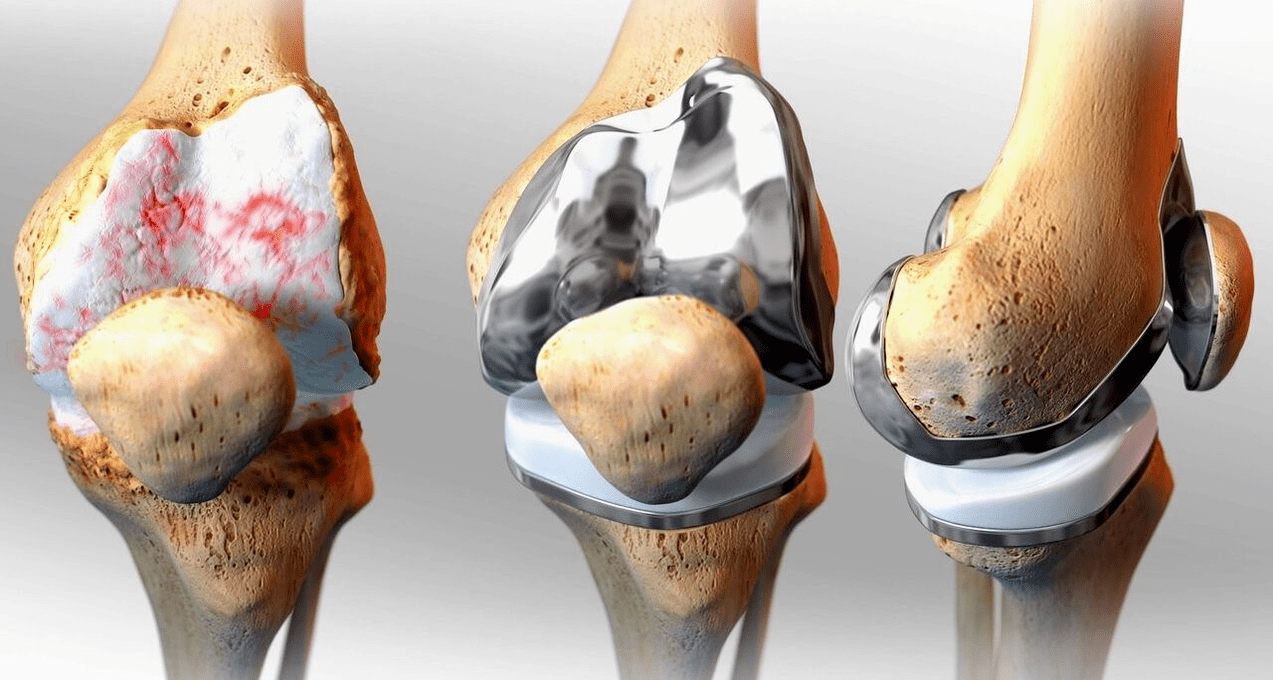

Surgical treatment and endoprosthetics

Endoprosthesis replacement is a common and effective surgical method for the treatment of severe gonarthrosis, which allows you to maintain limb mobility and the ability to lead a full life afterwards.It is a high-tech operation lasting about an hour and a half.In the postoperative period, long-term rehabilitation and development of the joint is necessary.After 25-30 years, when the artificial joint wears out, it must be replaced again.